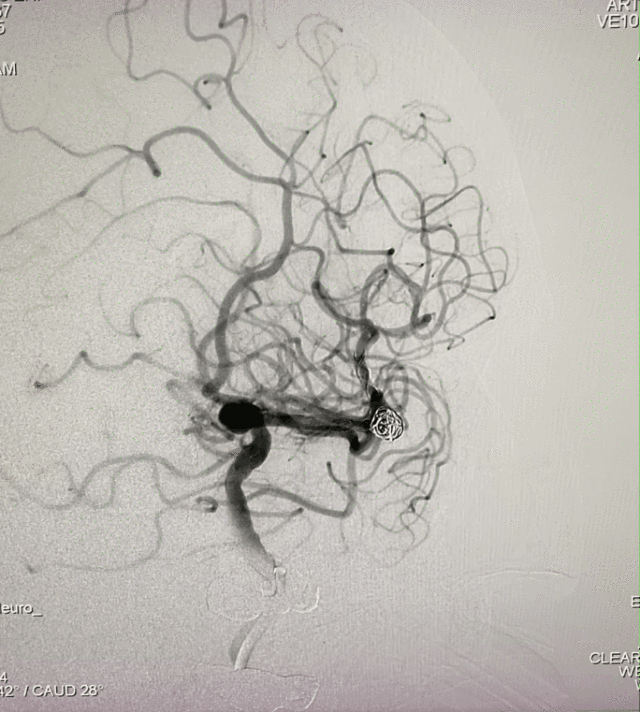

脑血管造影

左侧大脑中分叉处(上干)动脉瘤,夹层可能性大;瘤体4.3mm×5.1mm,瘤颈5.8mm。

远近端载瘤动脉直径分别为2.17mm、2.58mm。